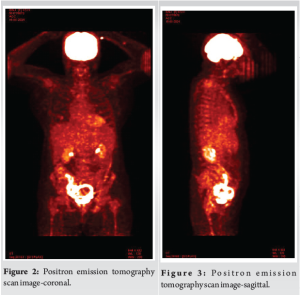

A 72-year-old female with a history of long-standing diabetes presented with fatigue, fever, and rashes on the upper limbs for 1 week. She denied any history of weight loss or loss of appetite. On physical examination, she exhibited no signs of distress, cyanosis, clubbing, raised jugular venous pressure, pedal edema, or lymphadenopathy. Her chest wall and spine were non-tender on palpation, and examinations of the abdominal, cardiovascular, pulmonary, and neurological systems were unremarkable. Laboratory investigations showed anemia (Hemoglobin: 6.4 g/dL) and severe thrombocytopenia (platelet count: 6000/μL) with a leukoerythroblastic blood picture on peripheral smear. Computed tomography (CT) scans of the abdomen and chest were unrevealing. Bone marrow aspiration and biopsy showed marrow spaces completely replaced by proliferating thin-walled vessels. In certain areas, clusters of plump spindle cells, likely endothelial cells, were observed. Immunohistochemical staining demonstrated that both the vessels and the spindle cells were strongly positive for CD31 and CD34, all suggestive of vascular neoplasia (Fig. 1). However, further positron emission tomography (PET) scan investigation revealed multiple non-avid lytic areas involving almost the entire visualized skeleton, suggestive of skeletal angiomatosis, and non-avid cystic lesions in the liver indicative of visceral angiomatosis, leading to the diagnosis of systemic cystic angiomatosis (Fig. 2-5).

The diagnostic findings that led to the differentiation of systemic cystic angiomatosis from vascular neoplasia included multiple non-avid lytic skeletal areas and non-avid cystic liver lesions on PET scan. The treatment with danazol and eltrombopag, although unconventional, was chosen based on the patient’s preference for conservative management.